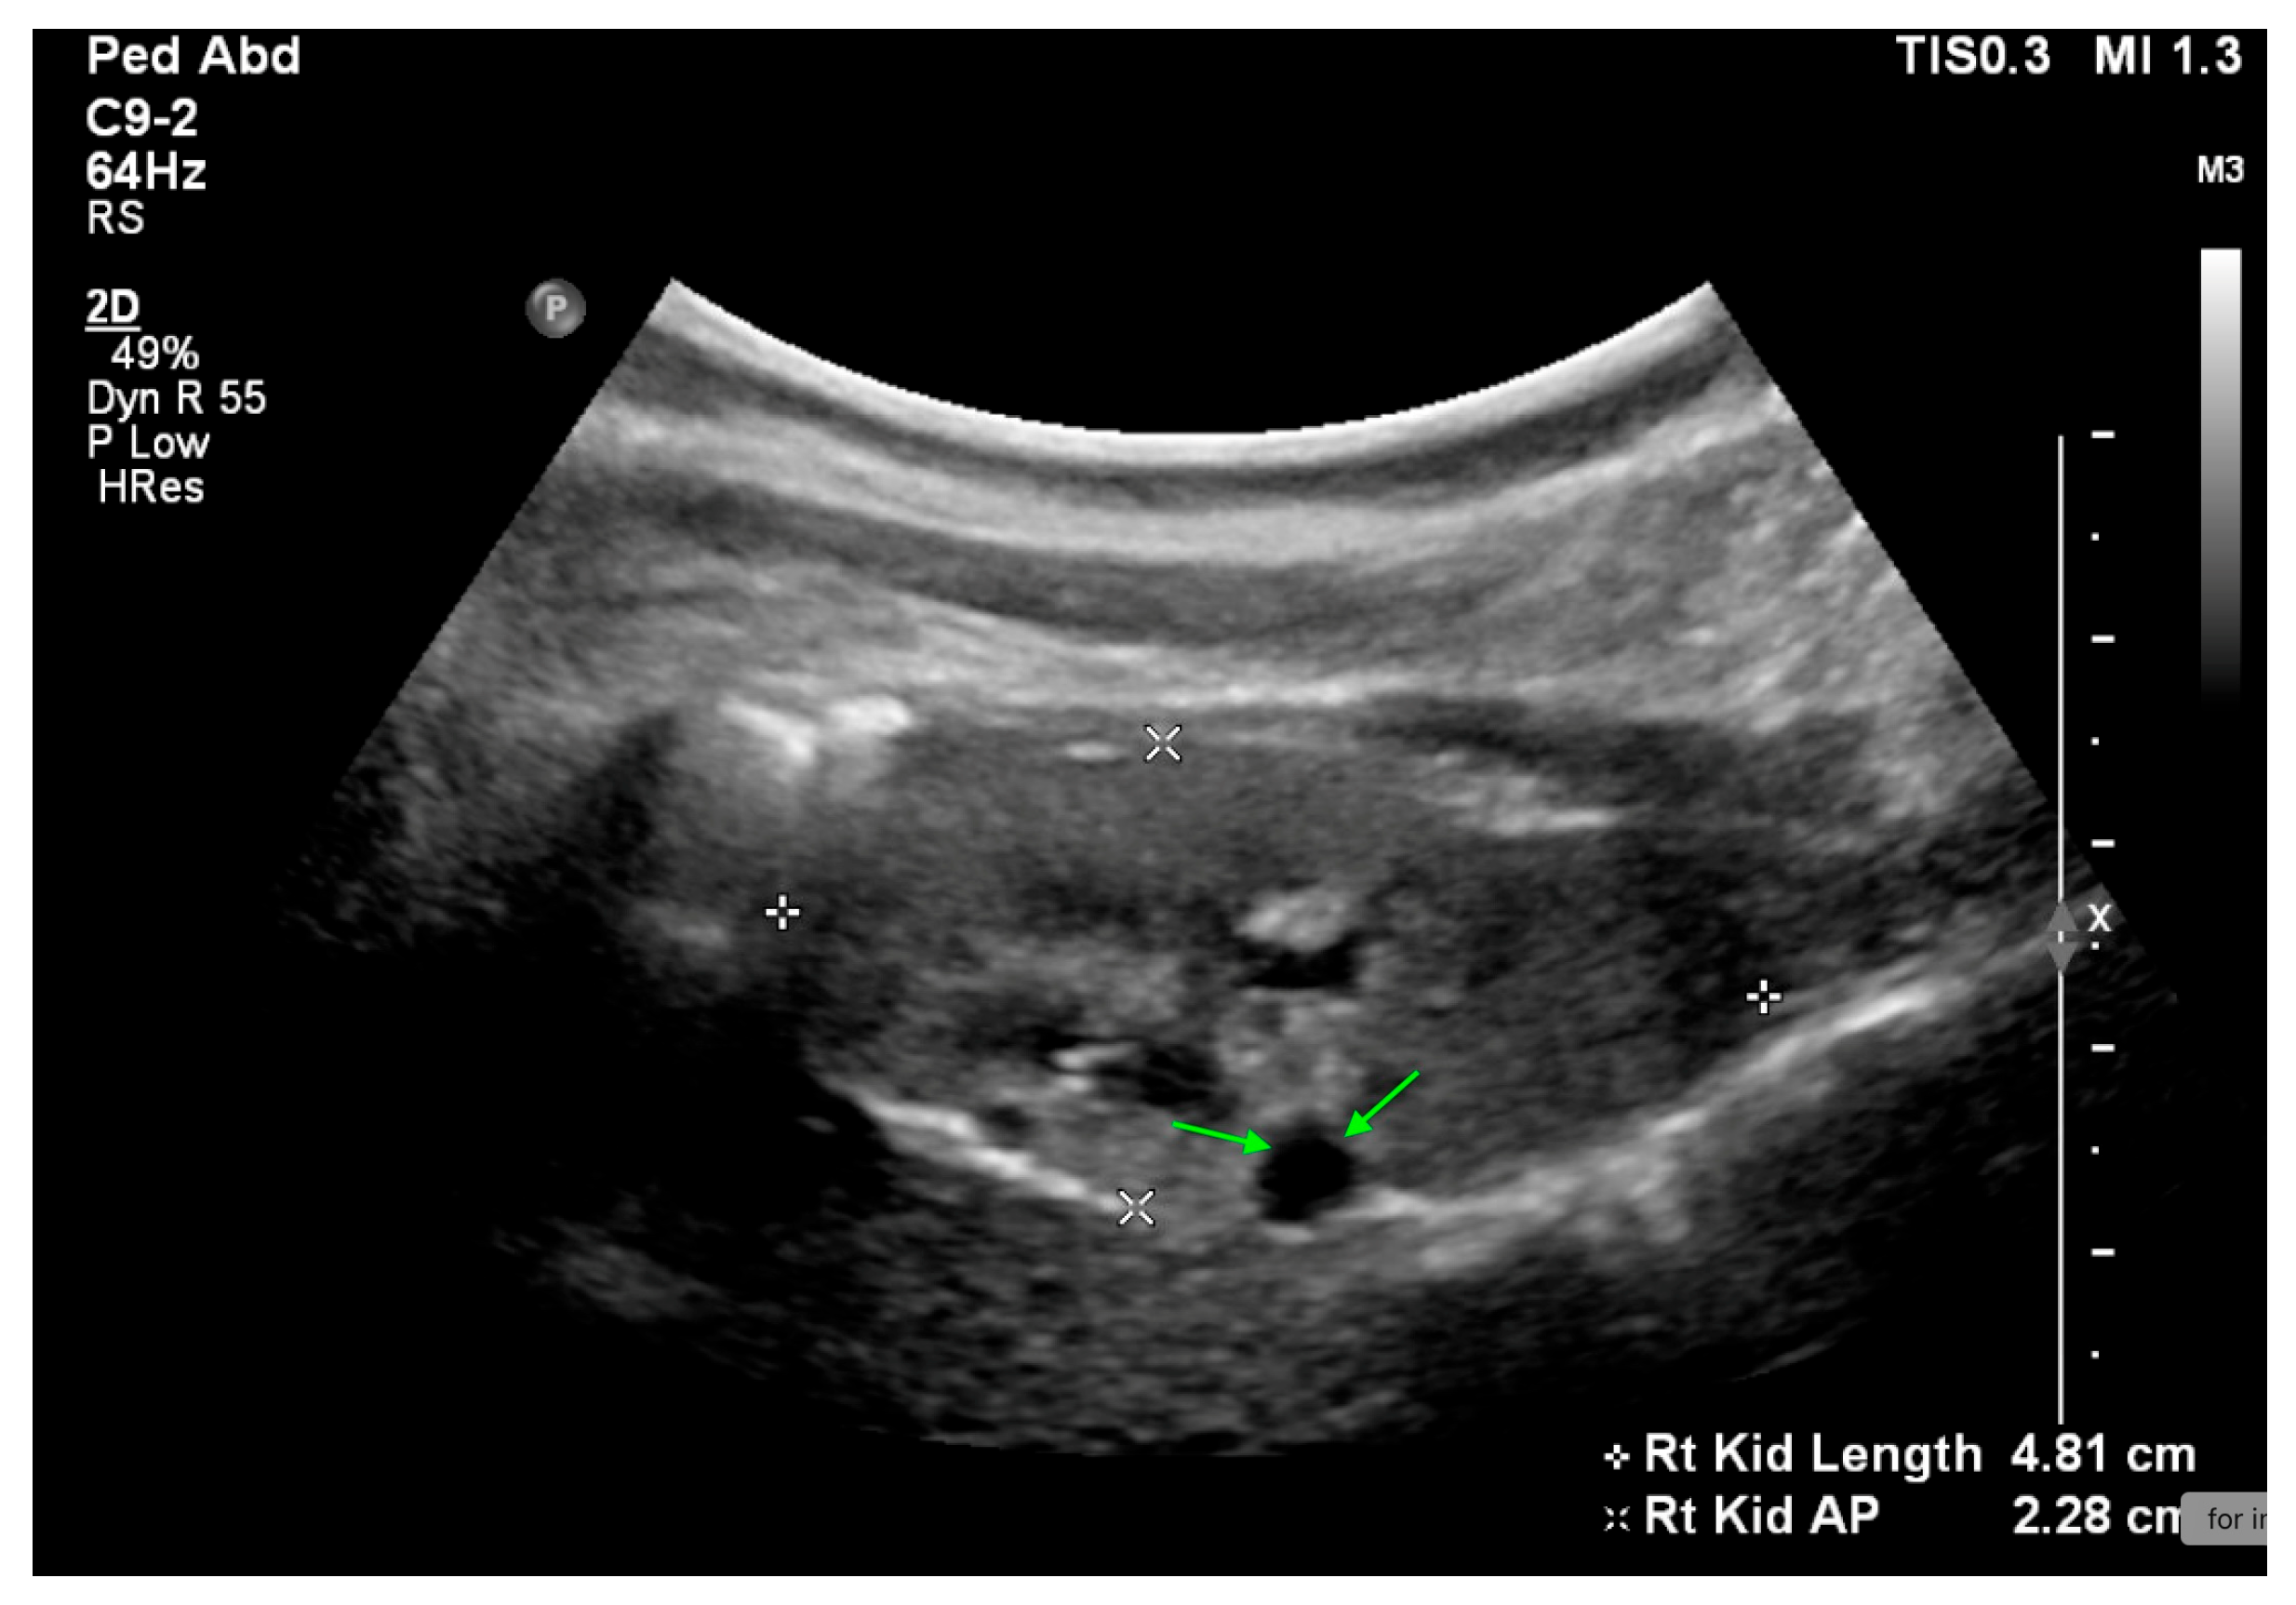

Figure 8. US reveals a small echogenic right kidney with a renal cyst (highlighted by green arrows) in a 2-year-old female.

Renal dysplasia is characterized by the presence of primitive ducts and cartilage. It is primarily diagnosed histologically, though US can reveal increased echogenicity and reduced kidney size, US may also show cysts of varying sizes and numbers (Figure 8).